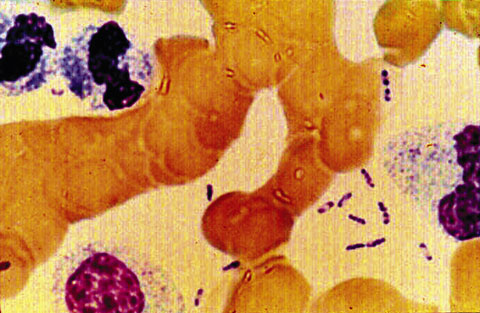

Growth from blood cultures is the most useful test for inhalational anthrax. This can occur within 6–18 hours of collection, although identification of bacilli can take a further 1–2 days. Sputum Gram stain and culture is usually not helpful as no pneumonic process is involved. Haemorrhagic meningitis is suggestive of anthrax, and bacilli might be seen in the cerebrospinal fluid. Gram stain (Box 2) and culture of vesicle fluid is useful for diagnosis of cutaneous anthrax.

2: Bacillus anthracus

Large gram-positive rods of Bacillus anthracus (Gram stain; original magnification ×1000). (Picture courtesy Dr Graeme Nimmo, Director of Microbiology, Princess Alexandra Hospital, Brisbane, QLD.)